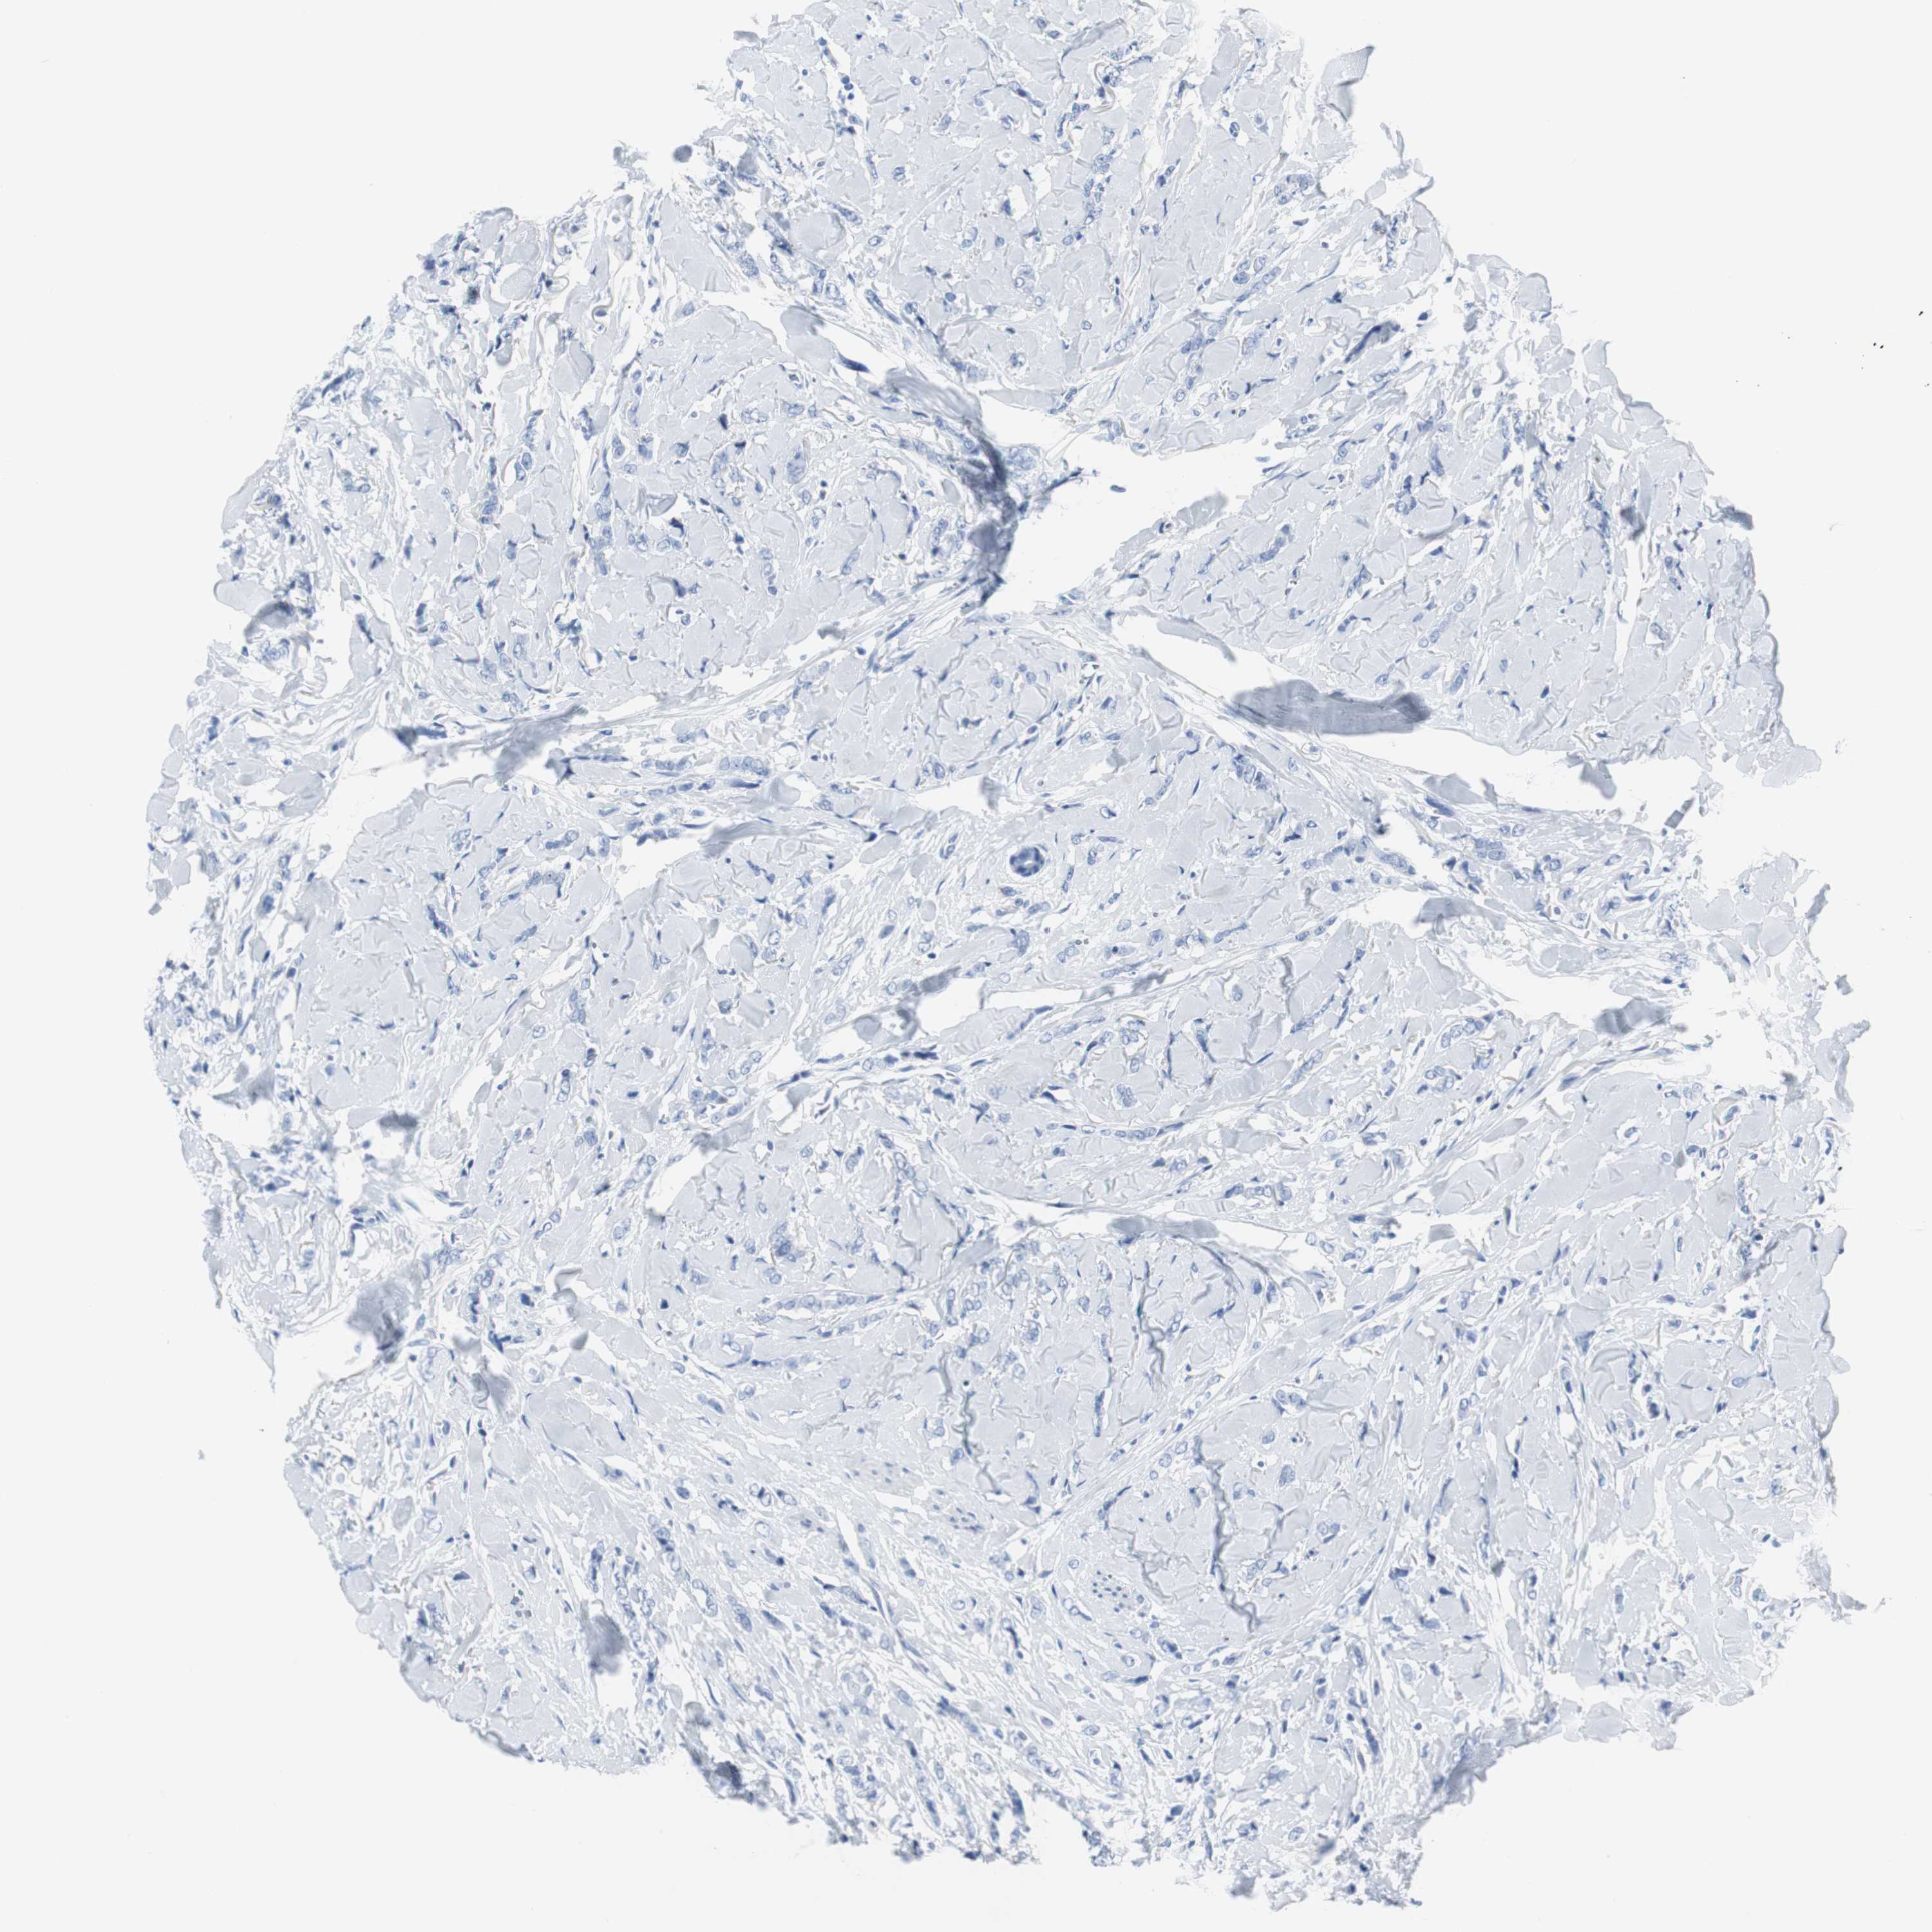

Breast cancer

Human cancer